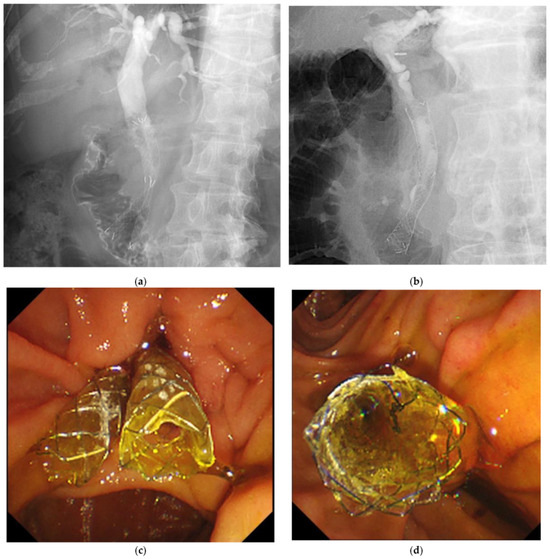

2.3. Procedure for DSS